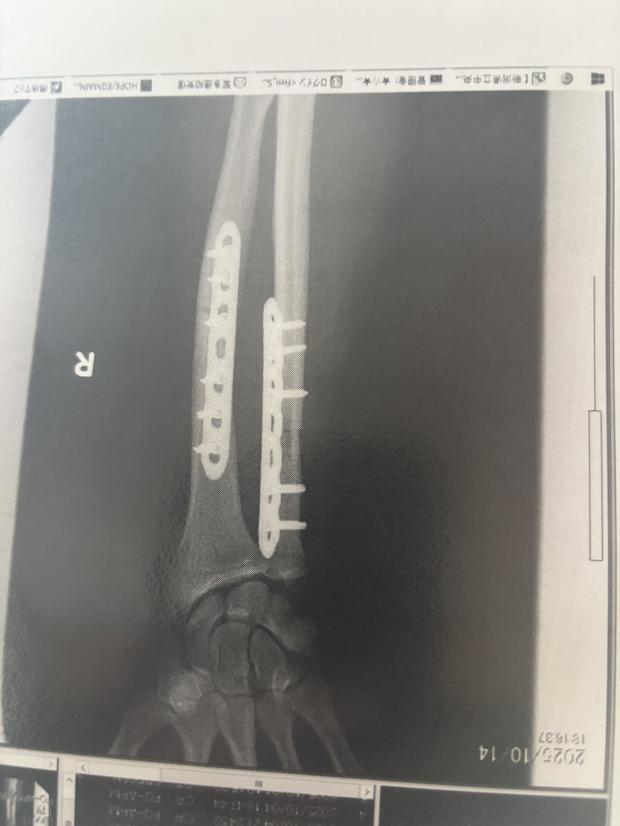

El a vorbit cu CNN din spitalul unde se recuperează de două săptămâni, după trei intervenții chirurgicale – inclusiv un transplant de os de șold pentru a acoperi o bucată din osul mușcat și montarea unor plăci metalice în braț.